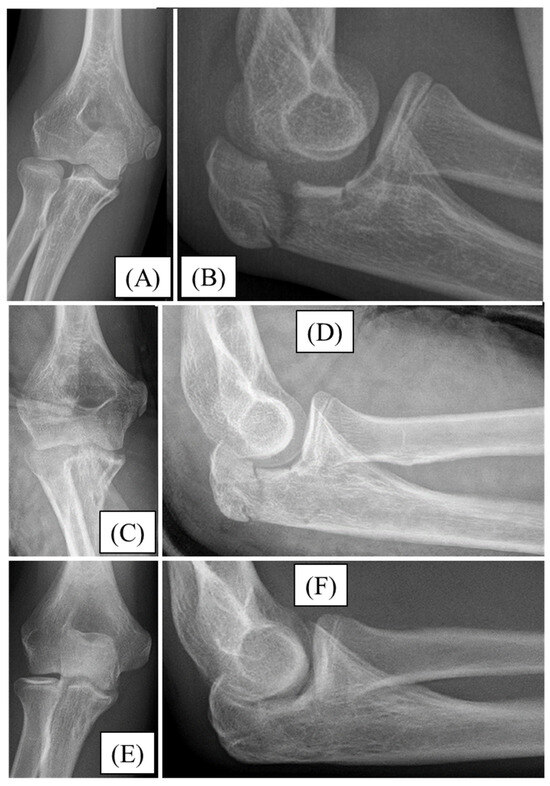

3.1. Case 1